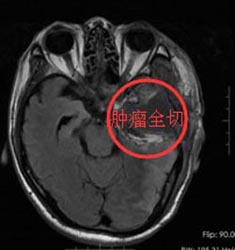

经家属同意后,由鲁主任主刀在唤醒麻醉下行“左侧颞叶占位性病变切除手术”。术前导航定位右颞肿瘤组织,术中给予唤醒麻醉,电生理监测运功中枢,避开功能区,术中快速病理检查考虑Ⅱ级胶质瘤,继续显微镜下分块切除,术中出血量少,过程顺利。术后病检结果与术前诊断相符。

手术后